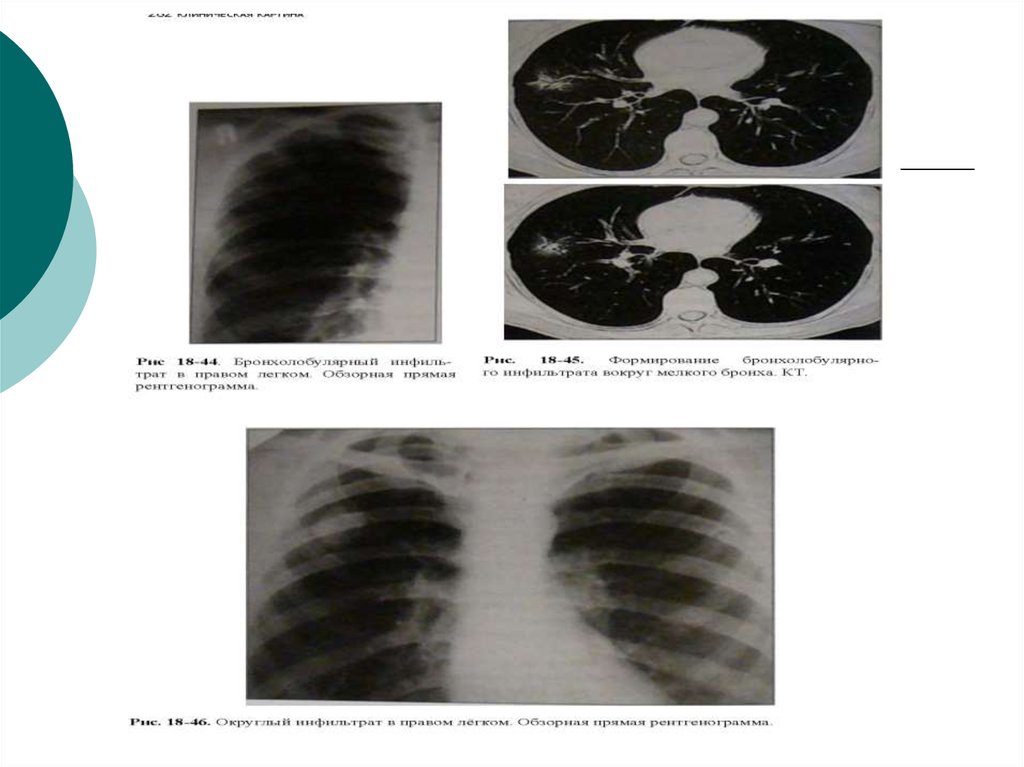

Иллюстрации по теме очагового и инфильтративного туберкулеза

Раздел: Фотодневник открытий